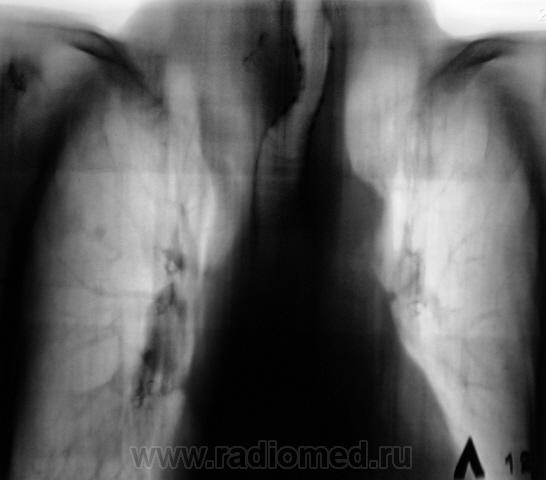

Экспансивно растущее об"емное образование верхнего средостения, неоднородной структуры за счет включений кальция. Состоит ли на учете у эндокринолога? Похоже на "ныряющий" зоб.

Думаю, что не "ныряющий", а конкретно "нырнувший", да там и "заночевавший" загрудинный зоб, включения кальция ничего хорошего не сулят. Согласен - УЗИ с, при необходимости,  биопсией.